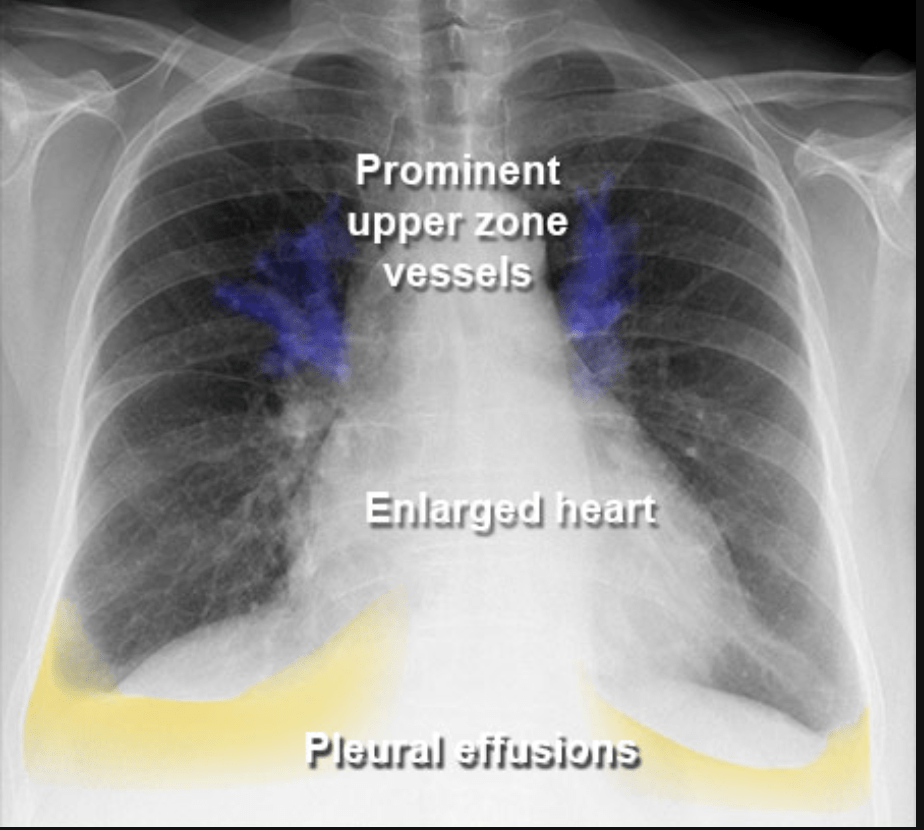

• How about this one?

Cardiomegaly - A big heart

What do we look for in a CXR?

• Water where it is not supposed to be.

Pleural Effusion